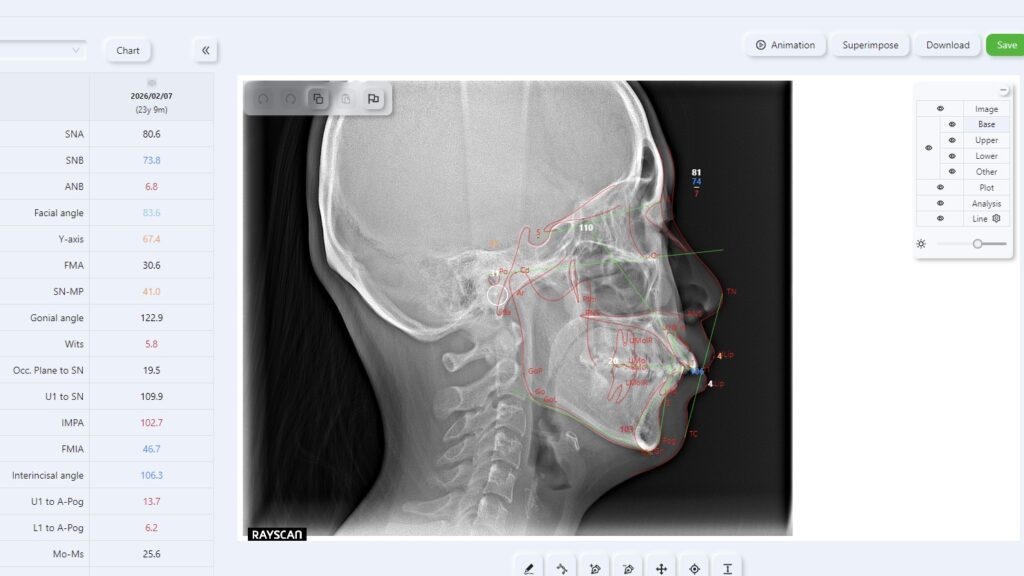

本当に必要なのは専門的な評価

矯正歯科医によるセファロ分析(頭部X線規格写真)では、Eラインだけでなく

・骨格の前後的なバランス

・上下顎の位置関係

・前歯の傾き

・唇の厚みと位置

などを総合的に数値で評価します。

これにより、「なぜ口元が出て見えるのか」「どこを改善すべきか」が明確になります。

自己判断や写真だけでは分からない部分こそ、専門的な分析が重要になる理由です。